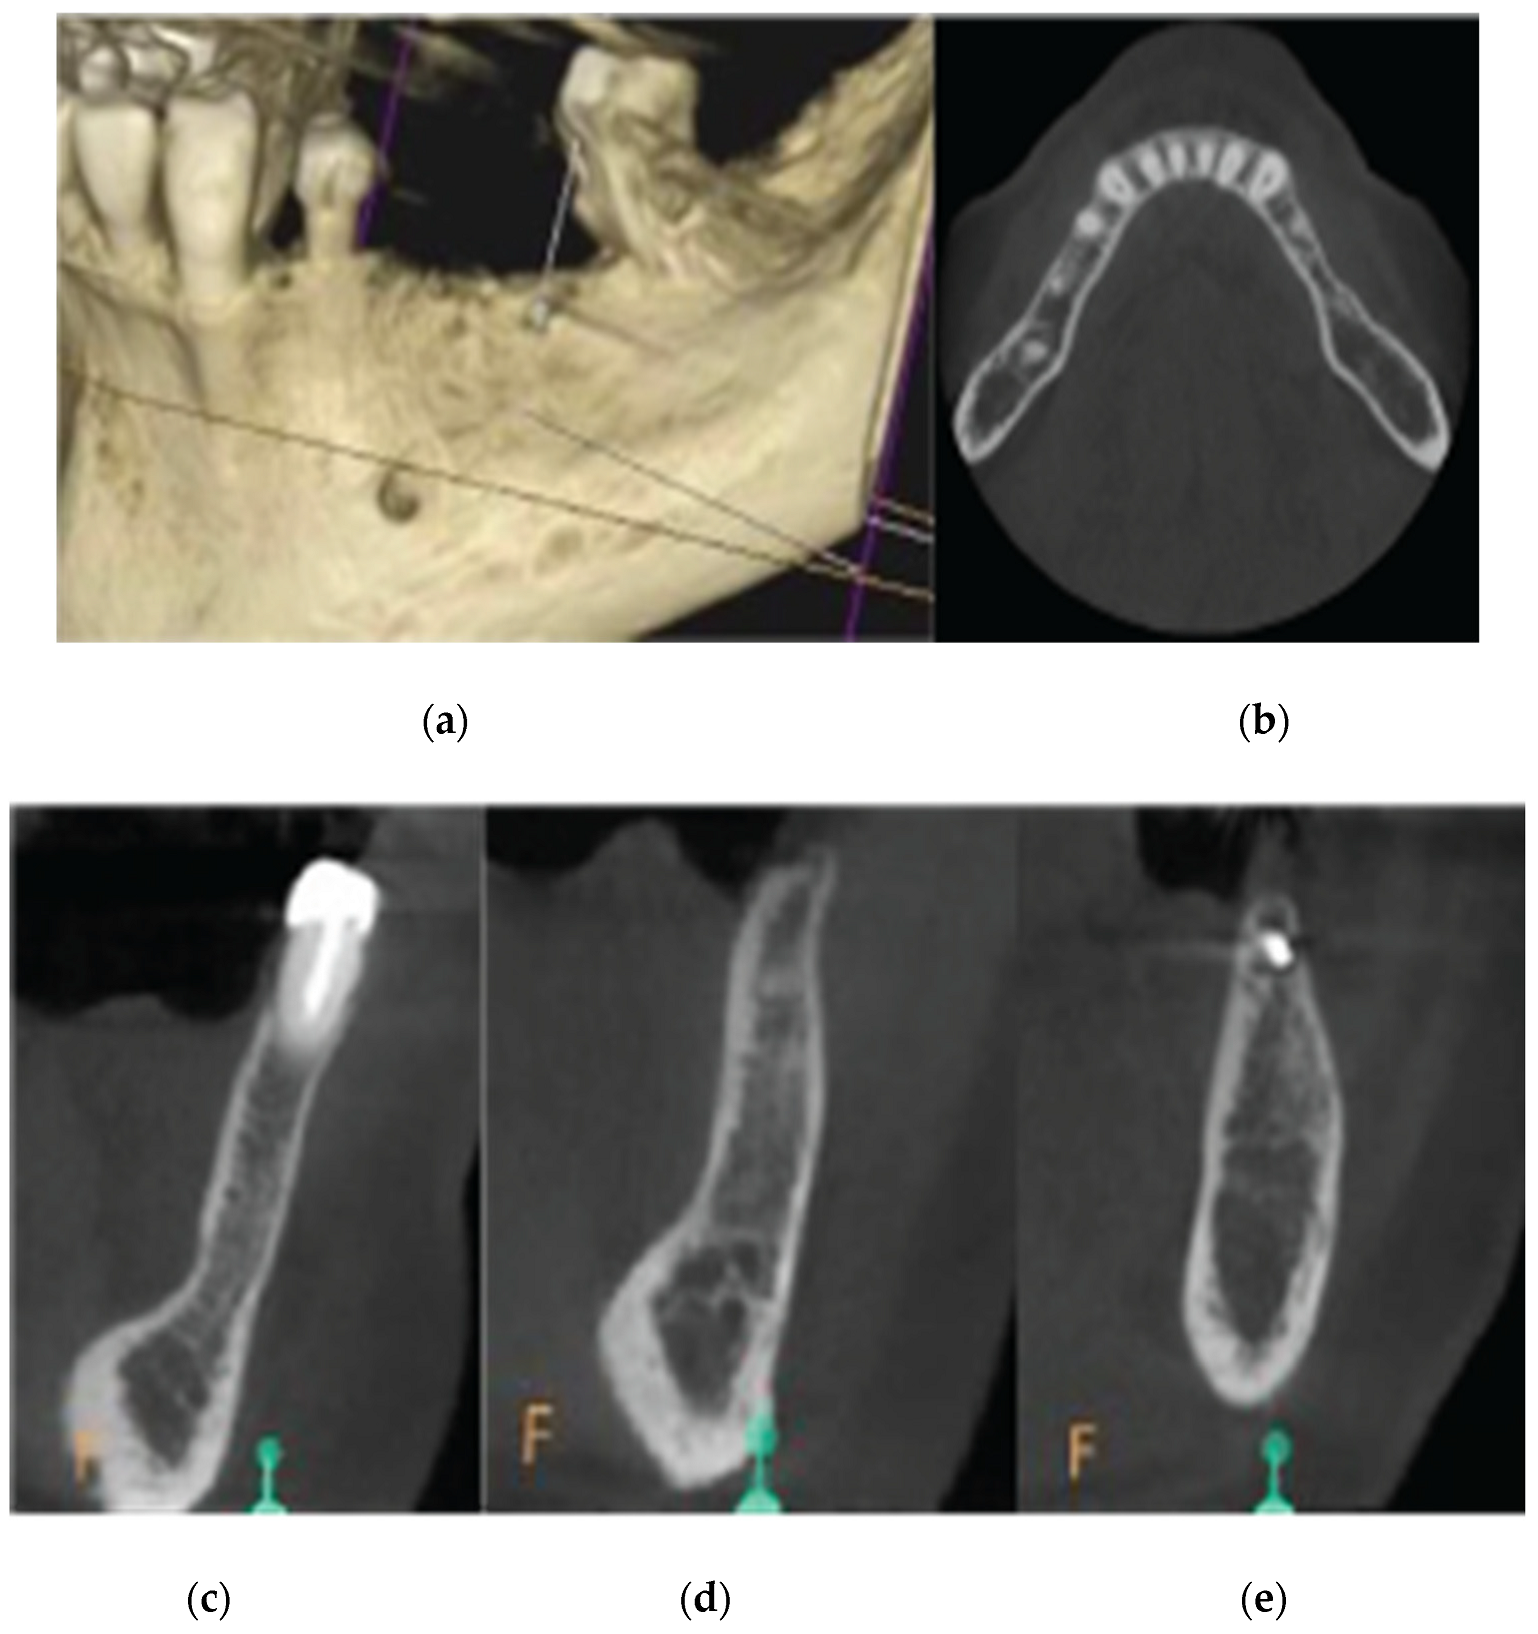

2.4. Case 2

2.5. Stage 1